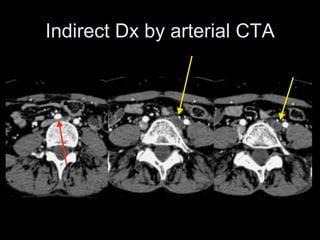

Indirect Dx by arterial CTA

• 120 cc contrast

• Monitoring delay = 40sec

• Smart prep at infrarenal IVC

28F May-Thurner syndrome,

CIV/EIV stent placement

3 years ago

Courtesy of Anne Chin, MD